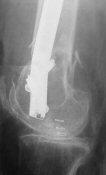

Attached are few examples from our Hospital:

A. Difficult reductions, even in retrograde nailing (my preference, easier control of "small" distal fragment) and it is much, much harder to do it anterograde (Alex, do you have one good case in your collection of anterograde nailing in very distal fractures - as you have suggested that I

should have done it in my previously posted case?

Malpositioning is much too common (recurvatum, varus - valgus).

B. Fixation loosening: distal cutting of the nail, non-unions do happen (cases attached).